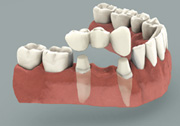

Tradional Crown and Bridge

Implant with a crown